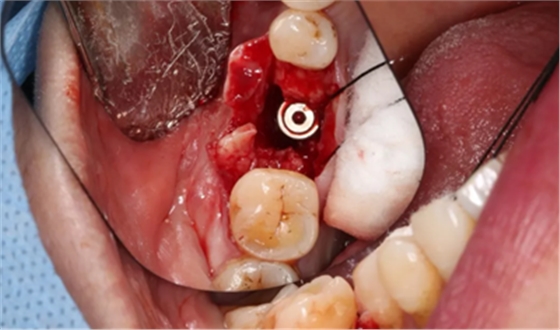

11、常规植入WEGO种植体一颗

牙槽嵴顶水平切口,翻瓣,牙槽嵴近中较远中丰满。

(摄于2017年4月14日)

植入国产威高(WEGO)5.0×11mm种植体,检查种植体位于理想轴位。